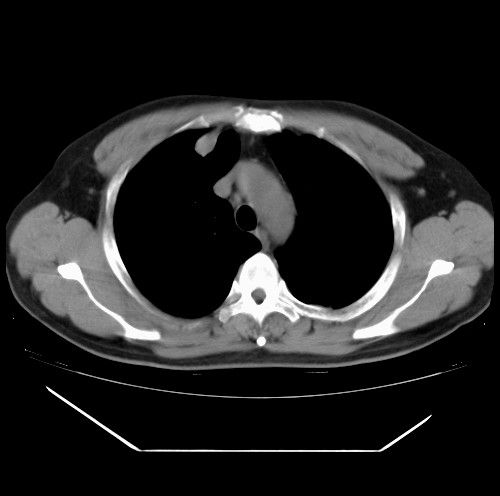

标题: CT22085:双肺多发结节

男,44岁,咳嗽,痰中带血2天。

病灶大部分位于胸膜下,结节大小相差不是很大,肺尖太干净。这种结核没见过,我认为可排除。

首先考虑转移,不除外肉芽肿、真菌感染。建议查其它。

除肺内及胸膜下可见多发大结节外,在肺小叶中心核、小叶间隔及支气管血管束上亦可见多方小结节,可以认为是随机分布。考虑转移可能性大。

仔细观察病灶形态,病灶边界部分清楚,结合临床症状,首先考虑转移,纵隔内多个肿大淋巴结影。

双肺血管纹理末端多发类圆形结节,边界光滑清晰 气管前腔静脉后淋巴结肿大

考虑转移瘤

本例双肺多发类圆形高密度灶,边清,结合病史多考虑双肺多发转移改变,可以结合实验室检查。